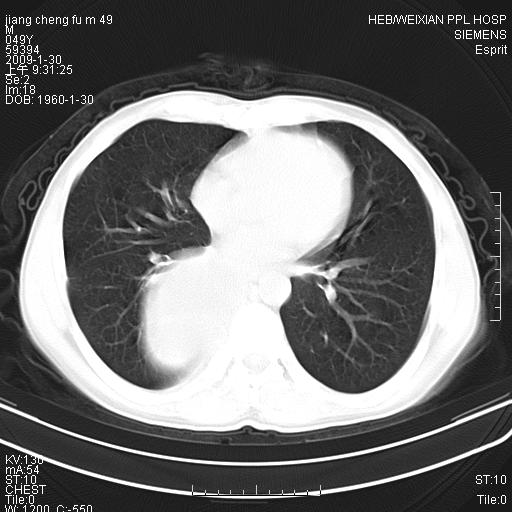

男性,49岁,主因胸痛,右肺呼吸音低。胸片提示肺占位

考虑右侧脊柱旁沟囊性病变。1:支气管囊肿或食管囊;2:神经源性肿瘤。

右后纵隔囊性占位;考虑为:1)淋巴管囊肿。2)食管囊肿。建议:进一步检查。

右后纵隔囊性占位,建议先做增强,后做穿刺活检。

在分析这个病变时,首先病灶边界清晰,但其内密度不均匀,有条索状状实性成分,肿块的外侧壁亦呈一不均匀的厚壁改变,因此支气管囊肿的可能性不大。主要考虑神经源性肿瘤(主要考虑神经鞘瘤,因为它囊变的机率比较高),其次考虑肺膈离征,行增强扫描如发现来自胸主动脉供血动脉血管可确诊。

考虑右侧脊柱旁沟囊性病变,囊骨有分隔,囊壁较厚。1:神经源性肿瘤;2:食管囊肿或淋巴管囊肿。支持!

囊状肿块内有线样软组织分隔,支气管囊肿及食管囊肿可不考虑。我考虑:1、囊性肺膈离征(需要增强扫描来排除)。2、神经鞘瘤。3、淋巴管囊肿。